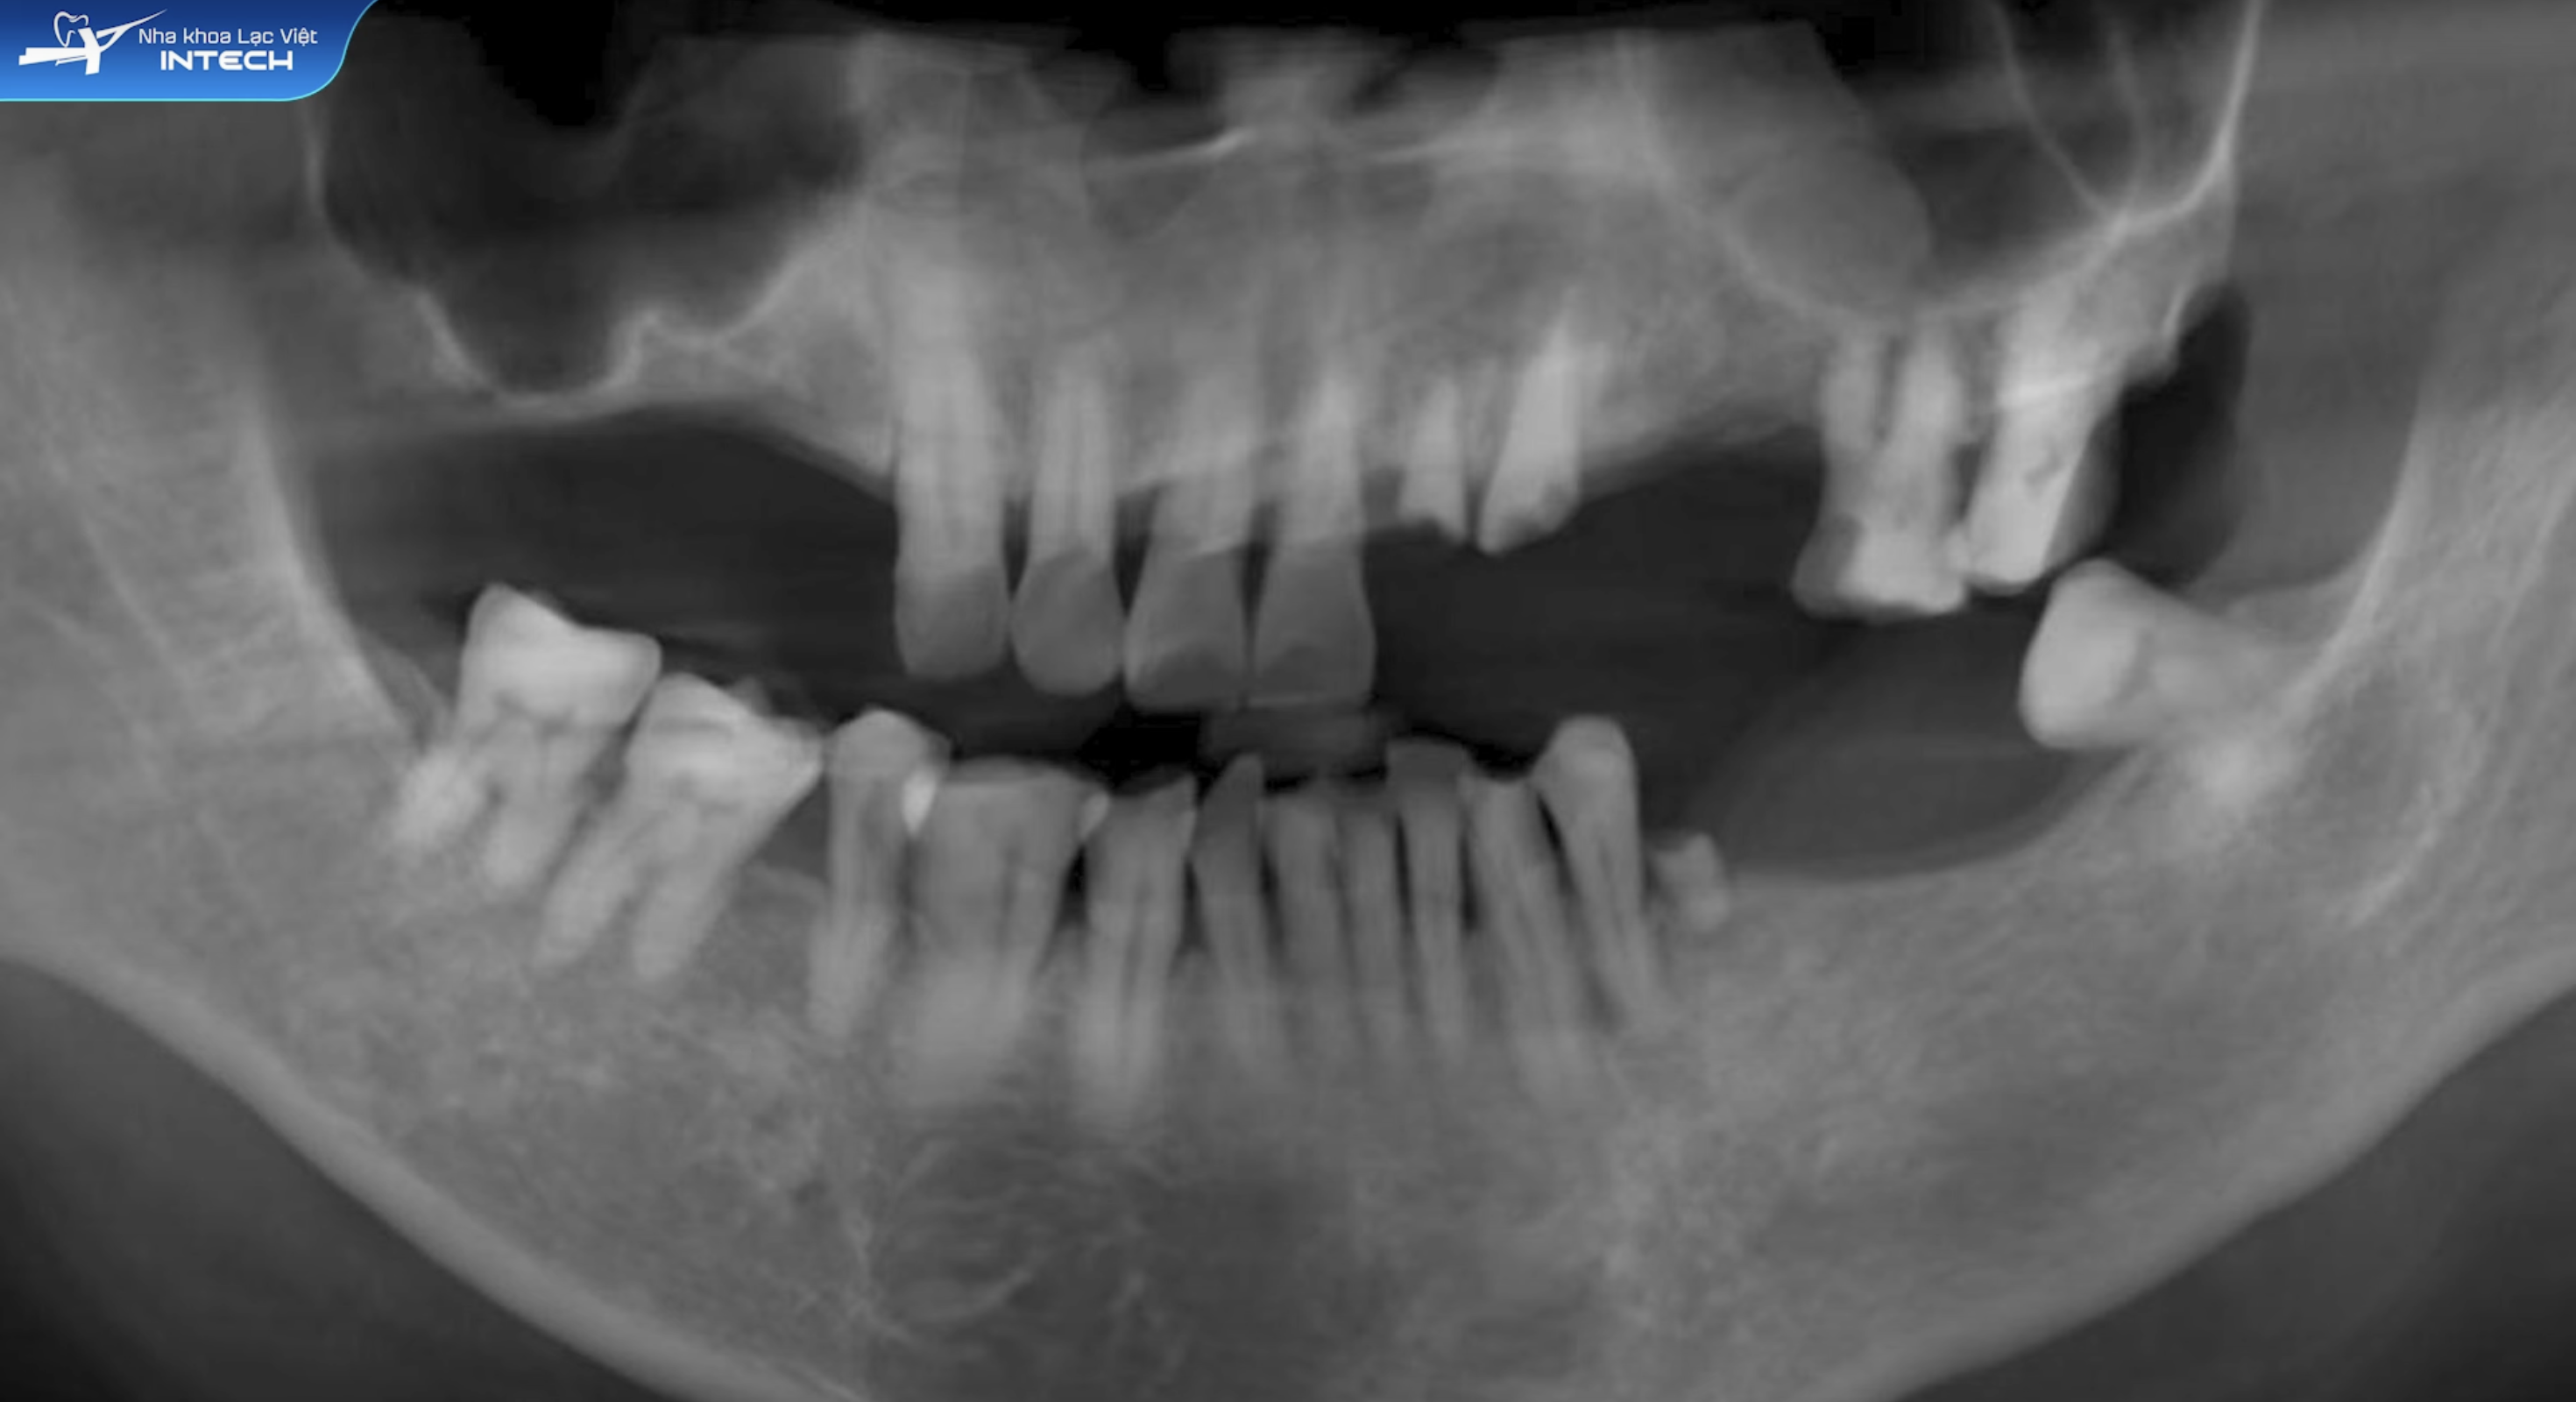

Tình trạng ban đầu của chú Thành rất đáng lo ngại. Chú đã mất gần toàn bộ răng hàm trên và dưới. Chú chỉ còn vài răng cửa yếu. Chú không còn điểm chạm nhai, khi cắn hàm dưới chạm vào lợi gây đau. Chú đã từng thử dùng hàm tháo lắp nhưng bất tiện, không hiệu quả. Giải pháp điều trị của bác sĩ rất tỉ mỉ. Bác sĩ lên kế hoạch phục hồi theo từng giai đoạn, giảm áp lực và đảm bảo an toàn. Tạm thời làm hàm tháo lắp để ổn định khớp cắn. Sau đó, tiến hành cấy implant ở các vị trí răng hàm quan trọng. Sau khi implant tích hợp xương, bác sĩ lắp răng sứ hoàn thiện. Cuối cùng, kết hợp bọc sứ răng cửa để cải thiện thẩm mỹ và khớp cắn.

Chú Thành gặp tình trạng mất gần toàn bộ răng hàm trên và dưới, không còn điểm chạm nhai